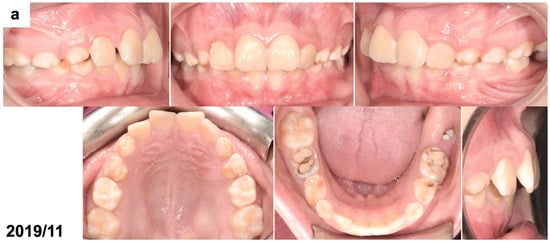

The patient’s face was symmetrical and proportional, and the profile was convex, with a slightly retruded chin. The lips were competent, and no oral dysfunctions or parafunctions were present. The patient was at the early mixed dentition period with all incisors and first permanent molars erupted, except for the mandibular left first molar. All deciduous canines and molars were present. The oral hygiene was poor, and the deciduous molars had large fillings. An extraoral examination revealed Class II dental relations with an increased overjet and overbite and a small space deficiency in the upper anterior segment. A small part of the clinical crown of the mandibular left first molar was visible through the gingiva (Figure 1a). Orthodontic documentation, including extraoral and intraoral photographs, diagnostic models, and a cephalometric radiograph, was taken before the start of the treatment. An extraoral examination revealed an enlarged, non-painful lymph node, differentiated with bone swelling by the lesion. The intraoral examination showed poor oral hygiene, teeth with numerous fillings and active caries, pathological abrasion, and no signs of soft tissue inflammation; the dimensions of the alveolar process were unchanged.

Figure 1.

(a) Intraoral photographs before surgical and orthodontic treatment. The patient was 8 years and 10 months old. (b) Panoramic radiograph before the treatment, presenting the odontogenic tumor in the left mandible molar region (OCx = complex odontoma). The patient was 8 years and 10 months old. (c,d) Intraoral photographs taken during the surgical removal of the tumor exposing the occlusal surface of the permanent lower left first molar (OCx = complex odontoma, LM1 = lower left first permanent molar). The patient was 8 years and 11 months old. (e) Panoramic radiograph after the surgical treatment and bonding of the orthodontic attachment (OA = orthodontic attachment). The patient was 8 years and 11 months old. (f) Panoramic radiograph 1 year after the removal of the tumor showing the orthodontic attachment bonded to the occlusal surface of the permanent lower left first molar (OA = orthodontic attachment). The patient was 10 years and 1 month old. (g) Intraoral photographs of spontaneously erupted permanent lower left first molar after removal of the orthodontic attachment. The patient was 10 years and 11 months old. (h) Panoramic radiograph 4 years after the surgical and orthodontic treatment (LM1 = lower left first permanent molar). The patient was 12 years and 7 months old. (i) Intraoral photographs 4 years after the surgical and orthodontic treatment showing the erupted permanent lower left first molar and its position in the dental arch. The patient was 12 years and 7 months old.